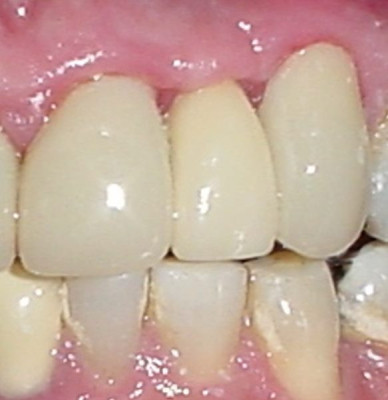

Control dos meses después nótese la mejor disposición de la encía

Post Image